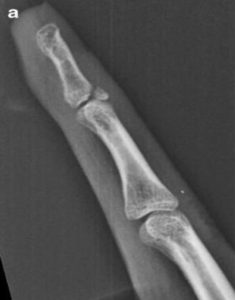

In contrast, *Figure A shows a bony avulsion following a football injury which led to a DIP lag of 26 degrees and was told only surgery could fix the issue. However, following being placed in an anti-swan orthosis for six weeks, his lag reduced to zero. Many bony avulsions are considered ‘stable’ with surgery rarely being a suitable option.

Examination of imaging is the initial step in determining the severity and future conservative management. When the symptoms of a mallet finger are present, an x-ray will be sufficient to determine the type of injury. Once the type of mallet is known, this introduces the immobilisation process which will involve positioning enough tension across the extensor tendon to allow the healing process to begin.